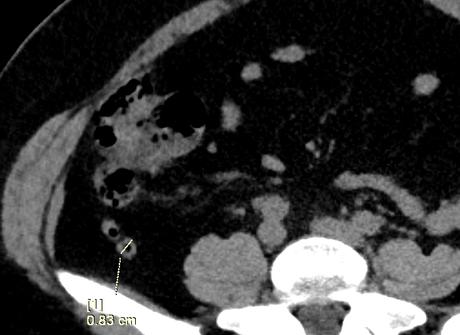

Se realiza búsqueda intencionada de la región de fosa iliaca derecha, apreciando una imagen tubular, en fondo de saco de ciego y presenta estriación de la grasa periapendicular la cual mide 10 mm en sentido anteroposterior, con presencia de un apendiculito en su interior de 5 mm, con densidad de 279 UH.

- HALLAZGOS EN RELACION A PROCESO APENDICULAR AGUDO, CON APENDICOLITO EN SU INTERIOR, SIN EVIDENCIA DE LIQUIDO LIBRE..